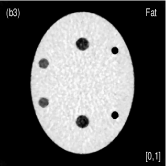

III.3 Catphan©600 phantom study

We acquired the Catphan©600 phantom data on a tabletop cone-beam CT (CBCT) system whose geometry matched that of a Varian On-Board Imager (OBI) on the Trilogy radiation therapy machine. We inserted iodine solutions with nominal concentrations of and into the phantom. There were pixels with a physical size of per pixel on the CB4030 flat-panel detector (Varian Medical Systems). The DECT measurements were obtained at kVp and kVp with a tube current of mA and a pulse width of ms. We acquired projections over in each scan. Using a fan-beam geometry with a longitudinal beam width of on the detector niu2010shading , We acquired projections with scatter contamination inherently suppressed. We used a contrast rod slice of the Catphan©600 phantom to evaluated the proposed method. We reconstructed attenuation images of size with a pixel size of . Fig. 3 shows the low- and high-energy CT images. Fig. 3(a) identifies the rods with labels: Teflon (labeled as ), Delrin (labeled as ), Iodine solution of (labeled as ), Polystyrene (labeled as ), low-density Polyethylene (LDPE) (labeled as ), Polymethylpentene (PMP) (labeled as ), Iodine solution of (labeled as ). Fig. 3(b) shows selected basis materials and ROIs in white dashed line circles: Teflon (ROI1), Delrin (ROI2), Iodine solution of (ROI3), PMP (ROI4), Inner soft tissue (ROI5) and Air (ROI6).

Fig. 4 shows the decomposed material images by the Direct Inversion, the PWLS-EP-LOOP and the PWLS-TNV- method. The left corners of the to the column of Fig. 4 show enlarged rods that are highlighted with white dashed boxes in decomposed material images. Table 2 summarizes the means and noise STDs of ROIs of decomposed basis material images. The volume fraction (VF) accuracies were , , and for the Direction Inversion, the PWLS-EP-LOOP and the PWLS-TNV- method, respectively. Compared with the Direct Inversion and the PWLS-EP-LOOP method, the proposed PWLS-TNV- method increases the VF accuracy by and respectively.

Table 3 summarizes the average electron densities of contrast rods and RMSE() of electron density for the three MMD methods. The RMSE() was , and for the Direct Inversion method, the PWLS-EP-LOOP method and the proposed PWLS-TNV- method, respectively. The proposed PWLS-TNV- method suppressed noise, decreases crosstalk and increased decomposition accuracy in the material images, while maintaining high image quality.